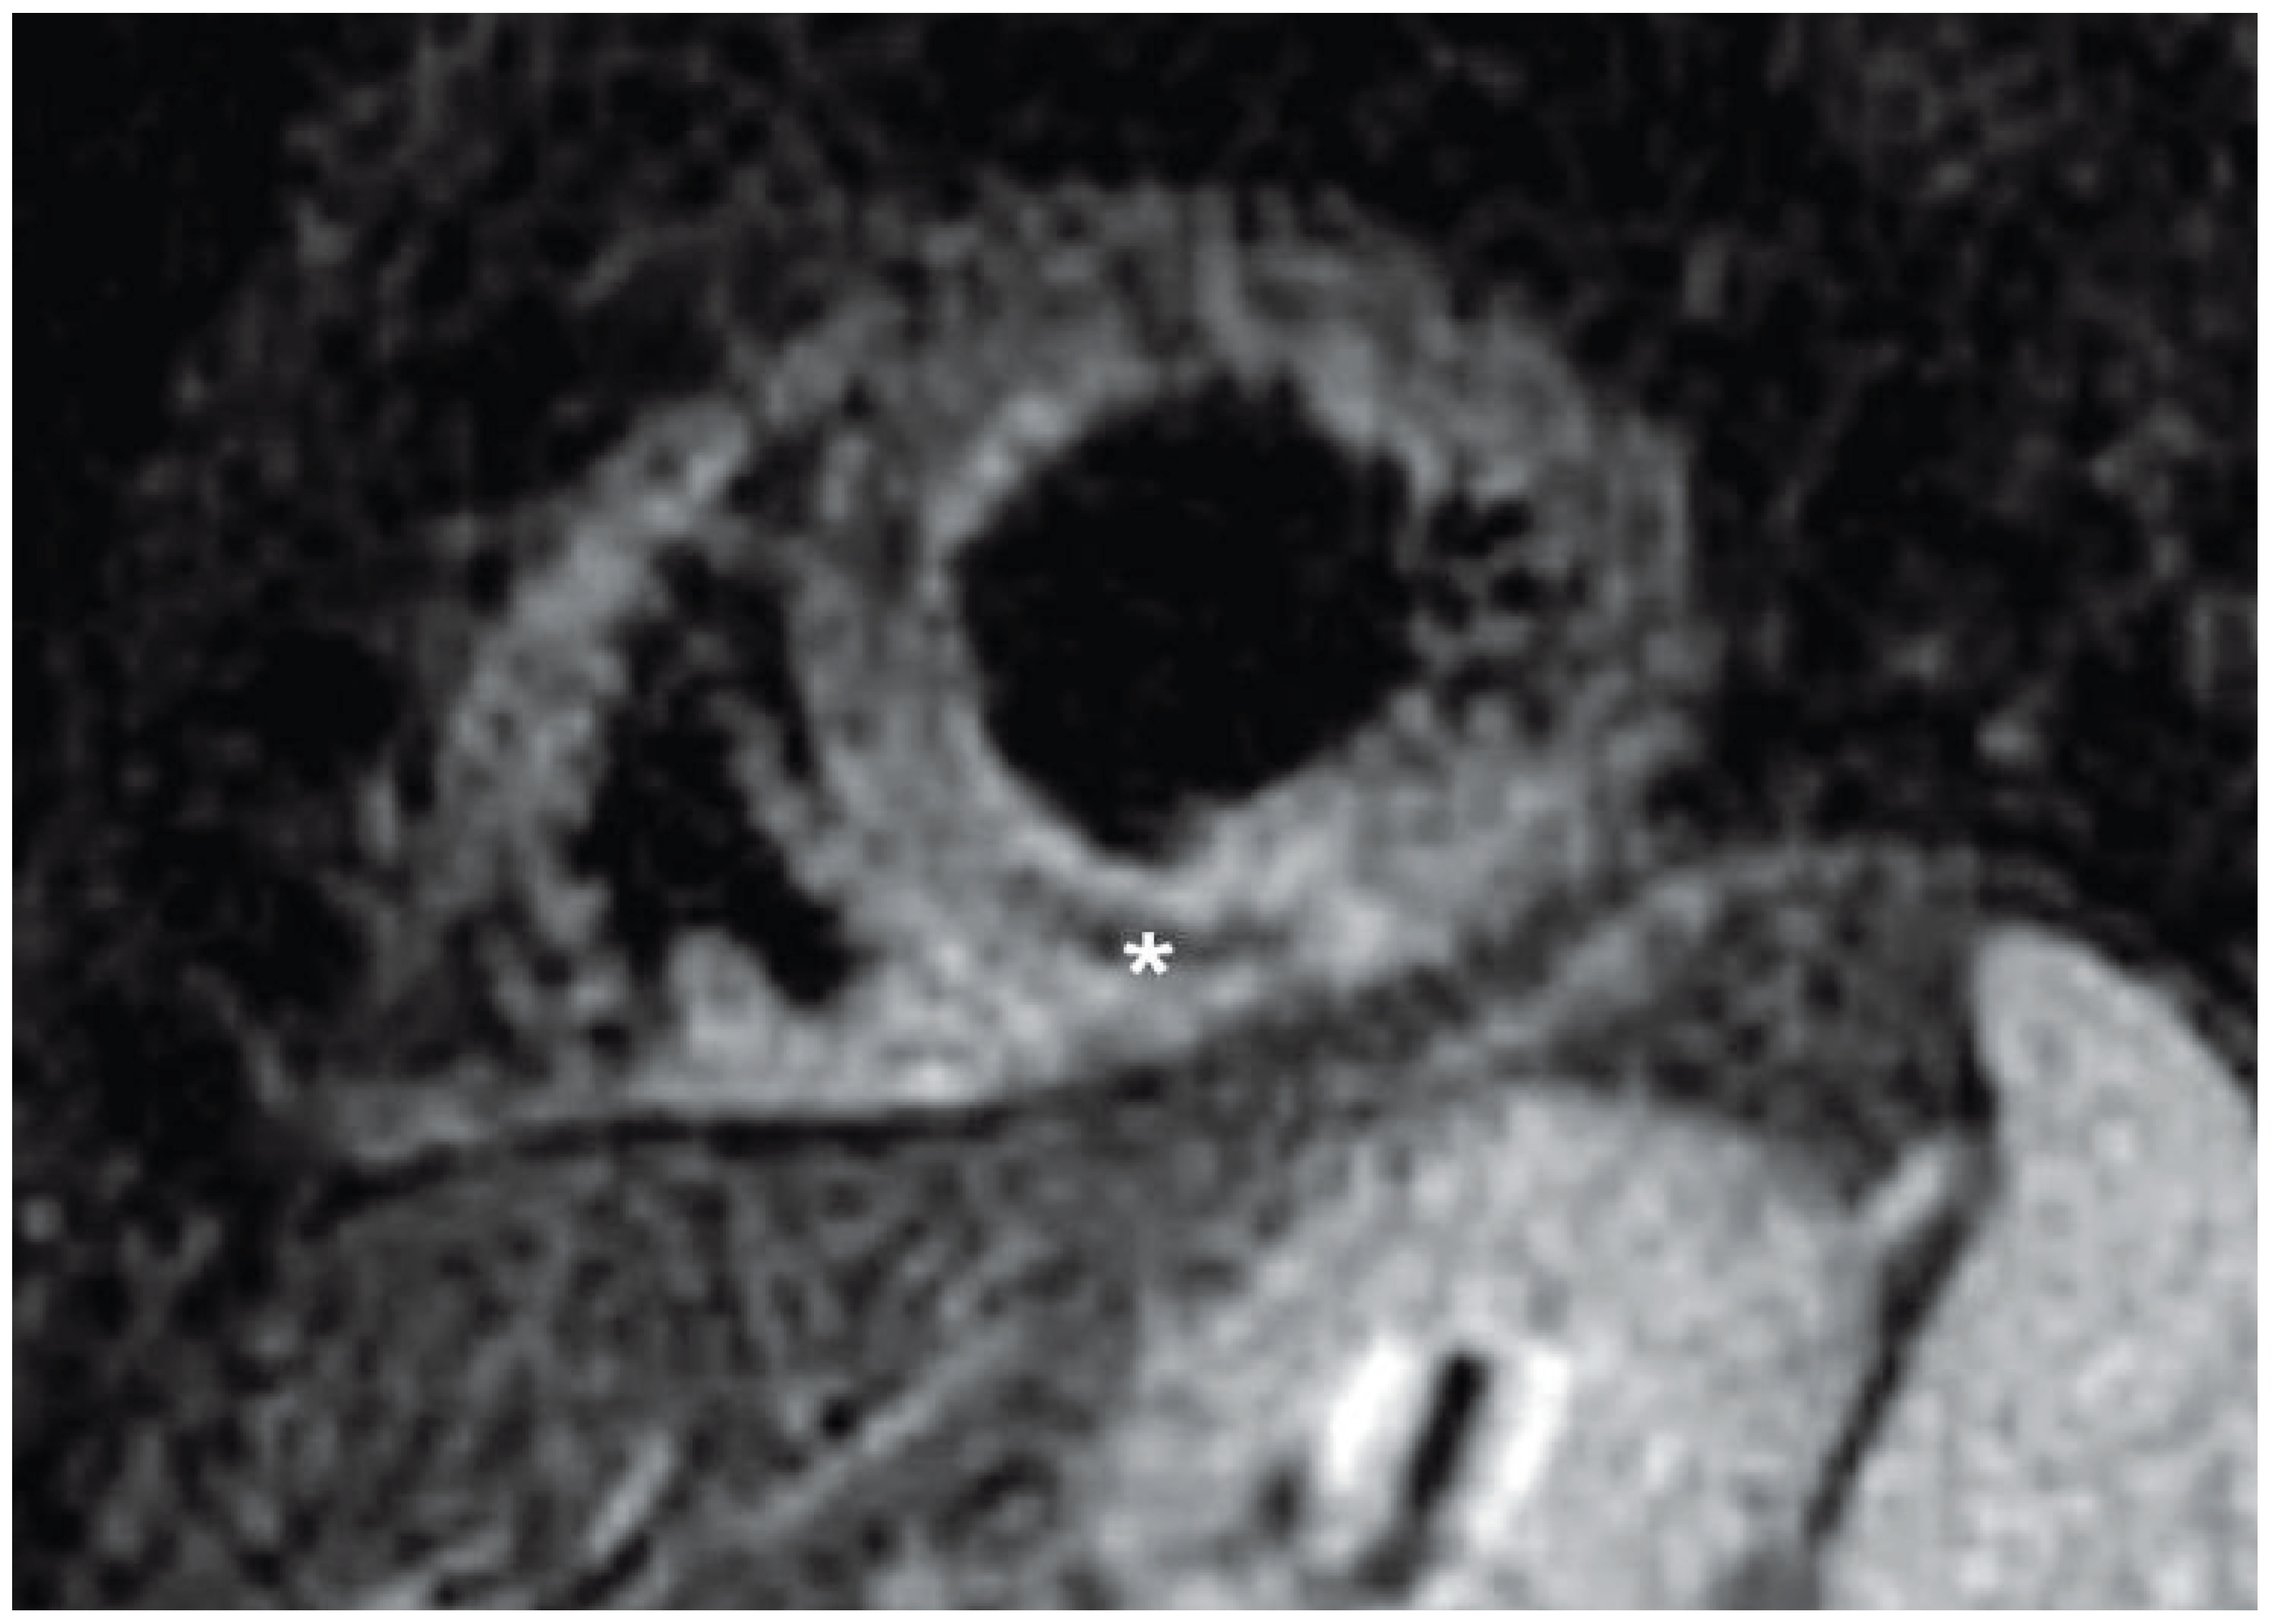

Figure 1) Also, T

1-weighted contrast-enhanced inversion-recovery gradient echo was used to assess myocardial delayed enhancement obtained 10 minutes after contrast injection. The entire inferior und inferolateral wall showed transmural delayed contrast enhancement with associated microvascular obstruction (MVO) in the distal inferior wall (

Figure 2A,B).